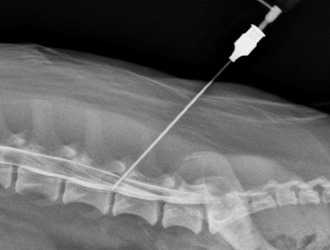

Раньше для выявления стеноза позвоночного канала обычно применяли миелографию - рентгенконтрастное исследование, при котором контрастную жидкость или воздух вводили в позвоночный канал посредством люмбальной пункции, а затем делали серию снимков. В настоящее время данная методика постепенно утрачивает свое значение из-за появления КТ и МРТ. Эти методы позволяют получить те же данные, но не имеют побочных эффектов и гораздо легче переносятся больными.